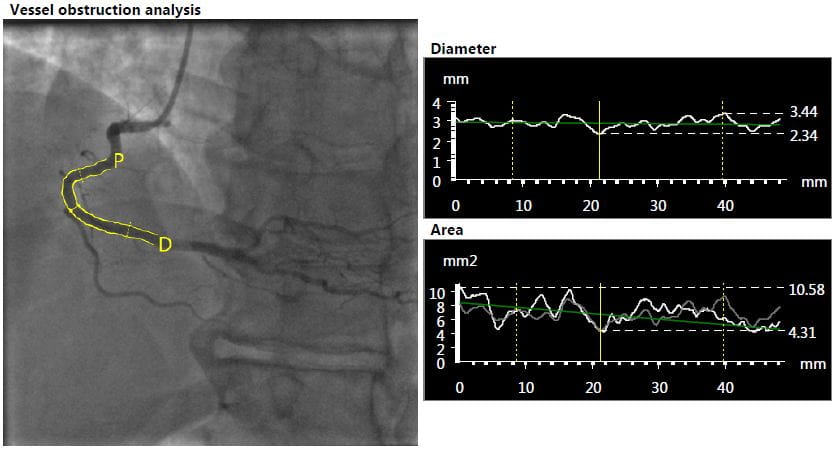

The Cardiovascular Phenomics Core Laboratory assesses, analyzes and improves quantitative coronary analysis (QCA) and quantitative vascular angiography (QVA). We provide objective and reproducible measurements of coronary, peripheral and other vessel dimensions.

- Assessing the vessel lumen diameter

- Evaluating restenosis after coronary or percutaneous interventions